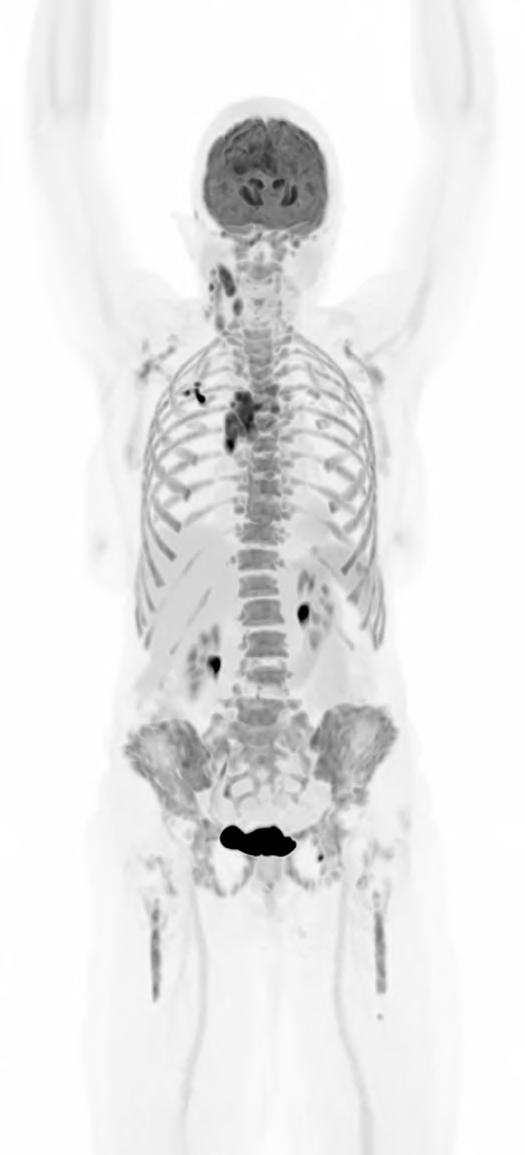

The Whole Picture: Total-Body PET and the Future of Biopharma

What if a clinical scan could transform biopharmaceutical innovation and patient care, streamlining drug development, clinical trials, and complex disease diagnosis? Total-body Positron Emission Tomography (PET) imaging is turning that vision into reality, offering a full-body, real-time view of human physiology.

Total-body PET is redefining what is possible in molecular imaging and biopharmaceutical development. This advanced PET technology can deliver full-body scans in minutes, with a sensitivity of up to 40x greater than conventional standard field PET scanners1 and potential for significantly lower radiation exposure. This opens exciting new avenues for research and discovery. It enables clinicians to study disease in real time across the whole body, revolutionising how we diagnose, stage and treat complex conditions like cancer, cardiovascular disease and neurodegenerative disorders. For patients, this means faster scans and earlier interventions, with the opportunity for more personalised treatments. For research and industry, it unlocks a powerful new platform for evaluating novel therapies, tracking their behaviour and accelerating their path to market.

Continued technological advances in hardware and software have led to a new generation of PET scanners with far greater sensitivity and resolution. While conventional PET relies on multiple bed positions and generating multiple images to acquire

a whole picture of the body, total-body PET has a field of view wide enough to take an image from head to toe in a single scan, and a detector capable of 40x higher sensitivity.¹ This means the whole body can be imaged faster, at higher resolution and in real-time. It also means lower doses of radiotracer are required to generate the same amount of detail (Table 1).1,3

Importantly, total-body PET does not replace conventional PET imaging. Conventional PET remains indispensable in clinical practice, especially when imaging needs are localised to a specific area of the body. But for complex diseases that span multiple organ systems or in cases where lower doses of radiation are required, total-body PET offers a transformative new lens:

• In oncology, total-body PET enables earlier detection of metastases and monitoring of tumours throughout the body, as well as increasing the potential for radiotheranostics (radiopharmaceuticals that can both detect and treat disease).7,8

• In cardiology, it helps us to understand how heart disease affects, or is affected by, other organ systems, supporting approaches to systems-based or preventative cardiovascular medicines.9

• In neurology, it allows the brain to be imaged at the same time as the rest of the body, which is critical for our understanding of complex neurodegenerative diseases.10

• In infectious disease and immunology, it offers a powerful tool for visualising infection and immune responses throughout the body, opening new avenues for treatment.11

• Finally, the higher sensitivity of total-body PET reduces the amount of radiotracer required for a high-resolution image, enabling paediatric studies in children and other patient populations where higher levels could be unsafe.12

In short, total-body PET is paving the way for a future where a systems-level understanding of human physiology may be possible. This will enable new insights into complex disease mechanisms and therapeutic targets where whole-body context is essential, or where study was previously difficult.

TRANSFORMING DRUG DISCOVERY

In addition to enabling more comprehensive study of complex disease mechanisms and therapeutic targets, total-body PET imaging is also set to change the way we assess and validate those targets and progress novel therapeutics through clinical trials. It does this by offering a more complete, accurate and efficient way to study their behaviour and role in the human body.

Total-body PET Provides Whole-body Systems Insight

Clinical images provided by Siemens Healthineers AG ©2025